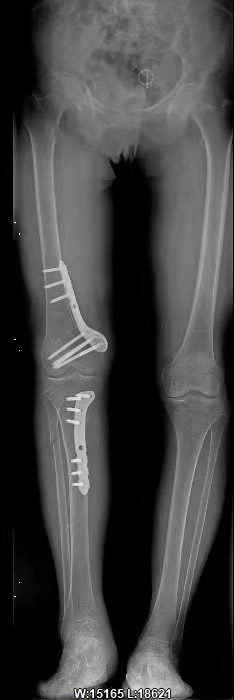

患者手术后的腿骨完全被矫正,与对侧角度相同

对于刘女士的手术,王天胜主任表示,如果不是运用了数字化技术,刘女士的手术就会非常复杂:“首先是手术的创伤面会非常大。在传统手术中,最起码要有一个20公分的切口,把患者的股骨全部暴露出来。同时术中要反复进行X射线检查,反复测量,确定截骨点和截骨角度,即便是这样也会有一定的偏差,因为都是人为来判断,与经过计算机精确计算是无法相比的。而在这次刘女士的手术中,创口只有5公分。另外,患者的内置钢板也是通过3D打印技术量身定制的,因此钢板的位置、形状以及螺钉位置都非常精确,可谓严丝合缝,这些都会大大缩短患者的恢复期,由原本需要半年到如今的4周就可下地走动。整台手术时间也由原来的5小时缩短为2小时,极大的降低了手术风险,减少副反应的发生。”